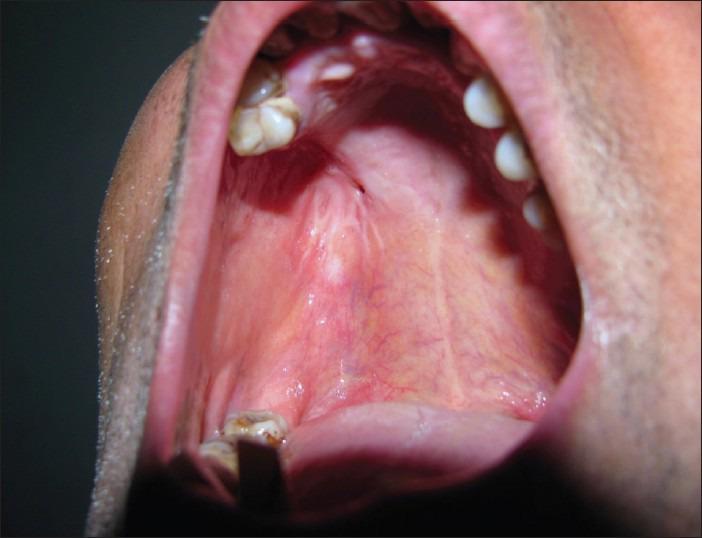

Rehabilitation of hemimaxillectomy patients can be challenging. The most common problem with prosthetic treatment in such patients is in getting adequate retention, stability, and support. The size and location of the defect usually influences the amount of impairment and difficulty in prosthetic rehabilitation. The obturator prosthesis is commonly used as an effective means for rehabilitating hemimaxillectomy cases. In cases of large maxillary defects, movement of the obturator prosthesis is inevitable and requires a form of indirect retention to limit the rotation of the prosthesis. The goal of prosthodontics is rehabilitation of missing oral and extraoral structures along with restoration of the normal functions of mastication, speech, swallowing, appearance, and so on. Malignancies are common in the oral region, which are treated through surgical intervention. Surgical intervention creates communication between the oral cavity, nasal cavity, and maxillary sinus. In such cases, it is very difficult for the patient to perform various normal functions like mastication, swallowing, speaking, and so on. Prosthodontic rehabilitation with obturator prosthesis restores the missing structures and acts as a barrier between the communication among the various cavities.

半侧上颌骨切除患者的康复治疗具有挑战性。此类患者进行修复治疗时最常见的问题是获得足够的固位、稳定和支持。缺损的大小和位置通常会影响修复康复的受损程度和难度。阻塞器假体通常作为修复半侧上颌骨切除病例的有效手段。在上颌骨大缺损的病例中,阻塞器假体的移动不可避免,需要某种形式的间接固位来限制假体的旋转。口腔修复学的目标是修复缺失的口腔和口外结构,同时恢复咀嚼、言语、吞咽、外观等正常功能。口腔区域恶性肿瘤很常见,需通过手术干预进行治疗。手术干预会在口腔、鼻腔和上颌窦之间形成通道。在这种情况下,患者很难进行咀嚼、吞咽、说话等各种正常功能。使用阻塞器假体进行口腔修复可恢复缺失结构,并在各个腔隙之间的通道起到屏障作用。